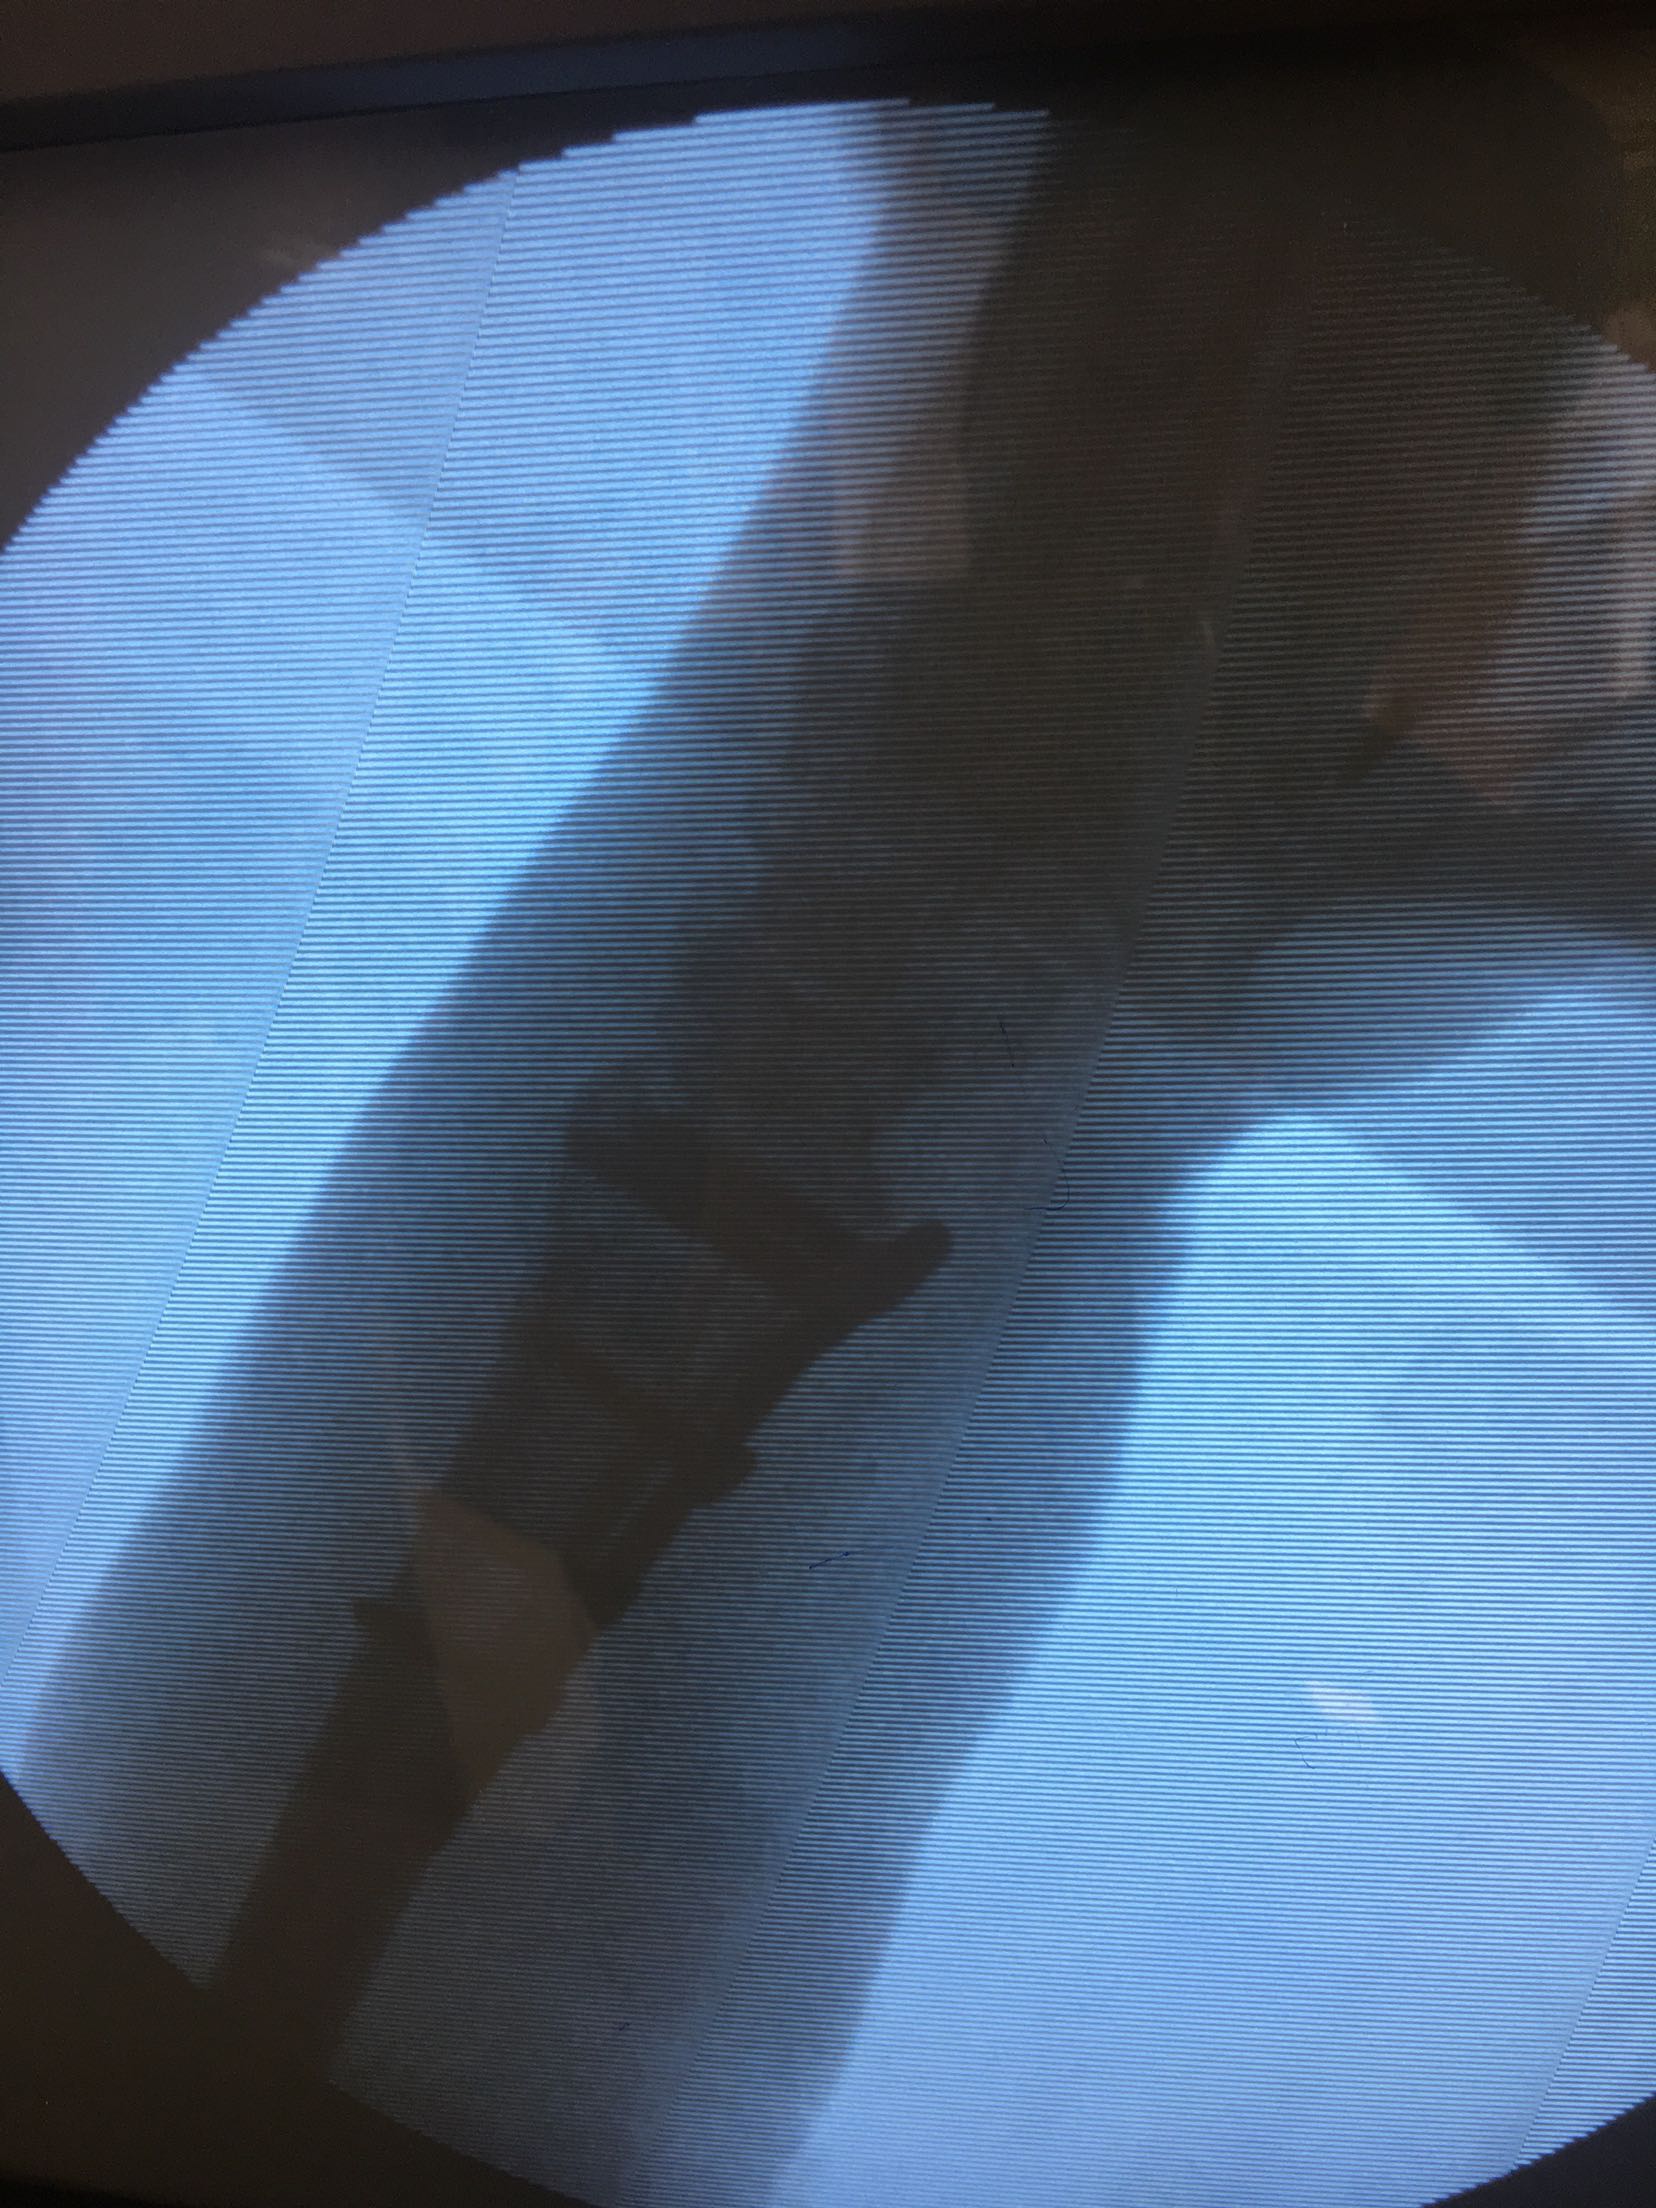

在臂丛麻醉下行切复内固定术,术后抗炎,消肿对症处理。